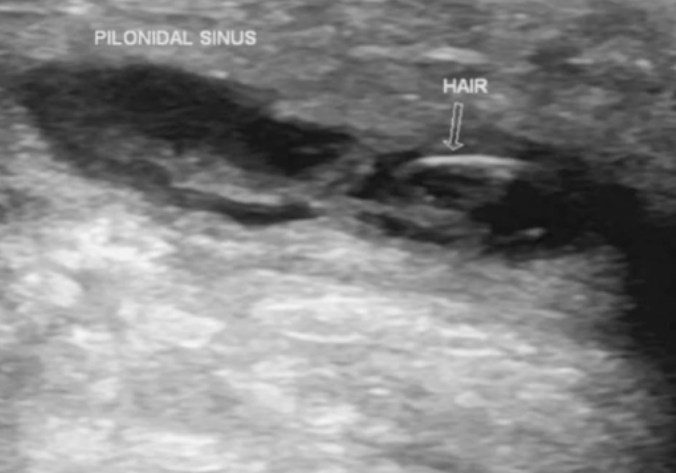

• Ultrassonografia (USG) de Partes Moles: É um exame útil que permite a visualização de todo o trajeto e auxilia na definição da extensão do acometimento. O cisto tipicamente se apresenta como uma coleção hipoecogênica, com heterogeneidade interna (devido aos folículos pilosos), podendo apresentar septações.

Retirado de: Patel M, Pilonidal sinus with abscess formation. Case study, Radiopaedia.org (Accessed on 16 Jan 2024) https://doi.org/ h0.53347/rID-17730 Observa cisto hipoecogênico, com heterogeneidade devido a visualização do folículo piloso. Eventualmente pode apresentar septação.